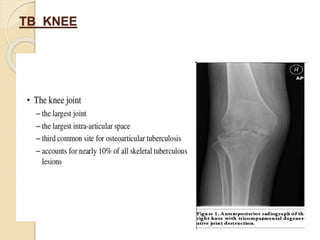

TB KNEE